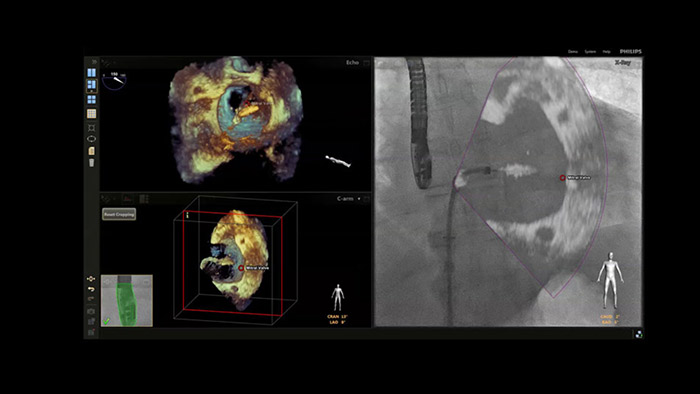

Nieuwe EchoNavigator met anatomische intelligentie

Om u extra inzicht te geven in de locatie van anatomische structuren, katheters en devices tijdens interventionele cardiale procedures, biedt de Philips EPIQ CVxi* ondersteuning bij multimodale besluitvorming.